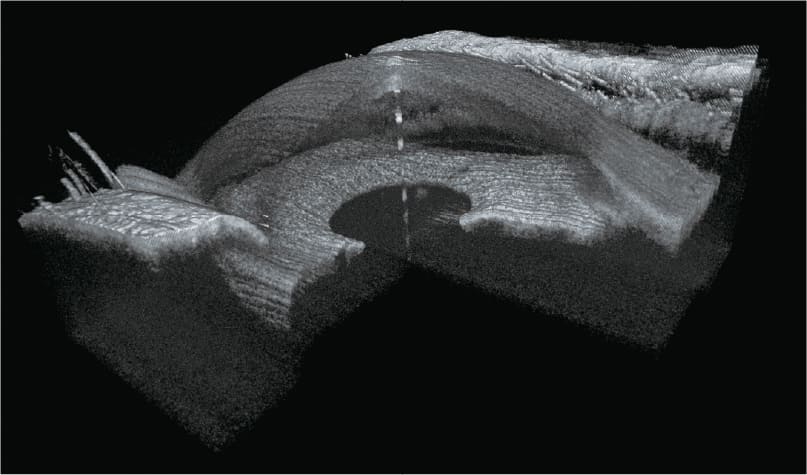

YAlkaid

100KHz Widefield

Full-Range SS-OCT

Das TowardPi 100-kHz-Breitband-Vollbereichs-SS-OCTA basiert auf vollständig eigenentwickelten Kernkomponenten und vereint hohe Scan-Tiefe mit exzellenter Auflösung in kurzer Erfassungszeit.

Es ermöglicht hochwertige OCT-Angiographie des vorderen und hinteren Augenabschnitts und liefert zuverlässige, detaillierte Bilddaten.

Intelligente Software mit Choroid-OCTA-Algorithmen, Flussquantifizierung, iSpot-Funktion sowie Analyse von Netzhautkrümmung und Gefäßdichte erweitert die diagnostischen Möglichkeiten und unterstützt ein modernes, präzises Krankheitsmanagement.

Klinische Bilder